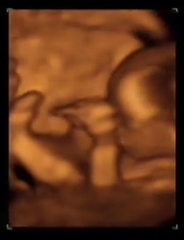

Desarrollo feto semana 14: La cara del bebé se humaniza

Tu bebé continúa su desarrollo en la semana 14 de embarazo. Su aspecto físico cambia de semana en semana. Ahora sus ojos están más centrados en su carita y el cuello se ha alargado. También crece de día en día. El tamaño de un bebé en la semana 14 de gestación es de unos 9 cm y pesa alrededor de 25 g.

En la semana 14 de embarazo, las orejas del feto se encuentran implantadas a ambos lados de la cabeza y también los ojos se han acercado; es decir, el bebé tiene ya una carita casi perfecta, tanto que ya se distingue el puente de la nariz. Incluso se puede ver que hace algunos pequeños gestos. Además, el cuello se ha alargado y el mentón ya no descansa sobre el pecho. Ya no parece que esté enroscado.

De todas formas su cabeza sigue siendo mucho más grande en relación al cuerpo y así será incluso años después de su nacimiento. Sus brazos han crecido y están más proporcionados con respecto al resto del cuerpo y han empezado a crecerle las uñas en sus deditos.

Si a la madre le hicieran una ecografía en la semana 14 de embarazo, el médico podría diferenciar las aurículas de los ventrículos. Su hígado es aún muy grande, porque tiene que fabricar células sanguíneas, aunque desde esta semana aproximadamente en esta tarea cuenta con la colaboración de la médula, que tendrá que asumir este papel cuando el bebé nazca. Pero de momento, solo practica.